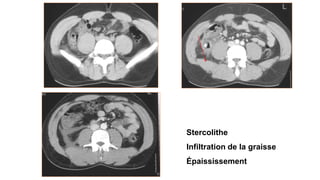

Stercolithe

Infiltration de la graisse

Épaississement

APPENDICITE

– Appendice de D> 6mm

– La paroi est épaissie et prise de

contraste

– Appendicolithe

– Infiltration de la graisse (péri cæcale,

pariétocolique)